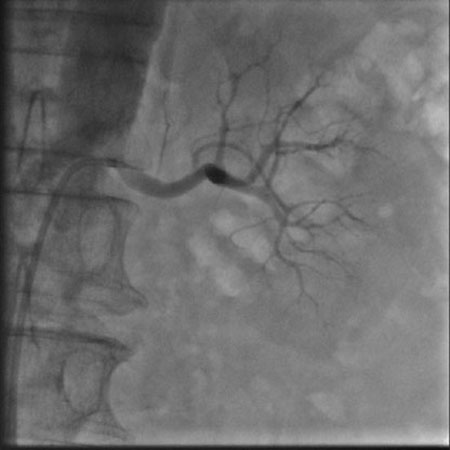

肾动脉造影(左)

肾动脉造影(左) 2月6日,我院心内科在上海普陀区中心医院心内科刘宗军主任指导下开展了我省首例肾动脉交感神经射频消融术。目前患者病情稳定,一周后复查动态血压,平均收缩压已从术前157mmHg降至137mmHg,患者已出院在继续随访中。 肾动脉交感神经射频消融术用于难治性高血压的治疗,于2008年在美国首先应用于临床,属介入手术,只需穿刺肾动脉进行手术,治疗完成后1—3月内患者血压即可明显下降,最大降幅可达30—40mmHg。术后患者服用少量降压药物即可将血压控制在良好水平,部分患者可以永久摆脱降压药物。从而避免了终生服用降压药带来的经济负担、生活不便和副作用影响。 心内科此次开展的肾动脉交感神经射频消融术在我省还属首例。目前国内仅北京、重庆、上海等少数医院开展该项手术。 高血压是最常见的心血管疾病,其中顽固性高血压患病率为5%-30%。肾动脉交感神经射频消融术的开展,对于提高高血压的控制率,减少和延缓并发症的发生具有重大意义,是近年来心血管领域最重要的进展之一。该手术的开展,属国内先进、省内领先的行列。(心内科 李燕萍 郝应禄) |